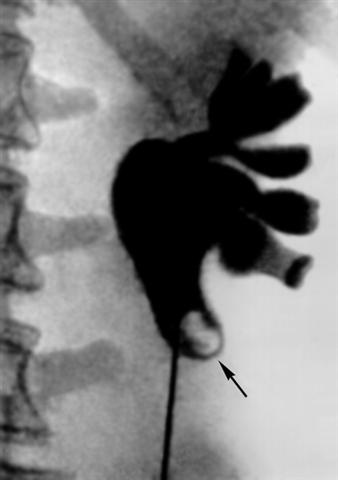

Рис. 2. Рентгенограмма левой почки при почечно-каменной болезни: почечные чашечки и лоханки расширены, в лоханочно-мочеточниковом сегменте виден дефект наполнения, образованный камнем (указан стрелкой).